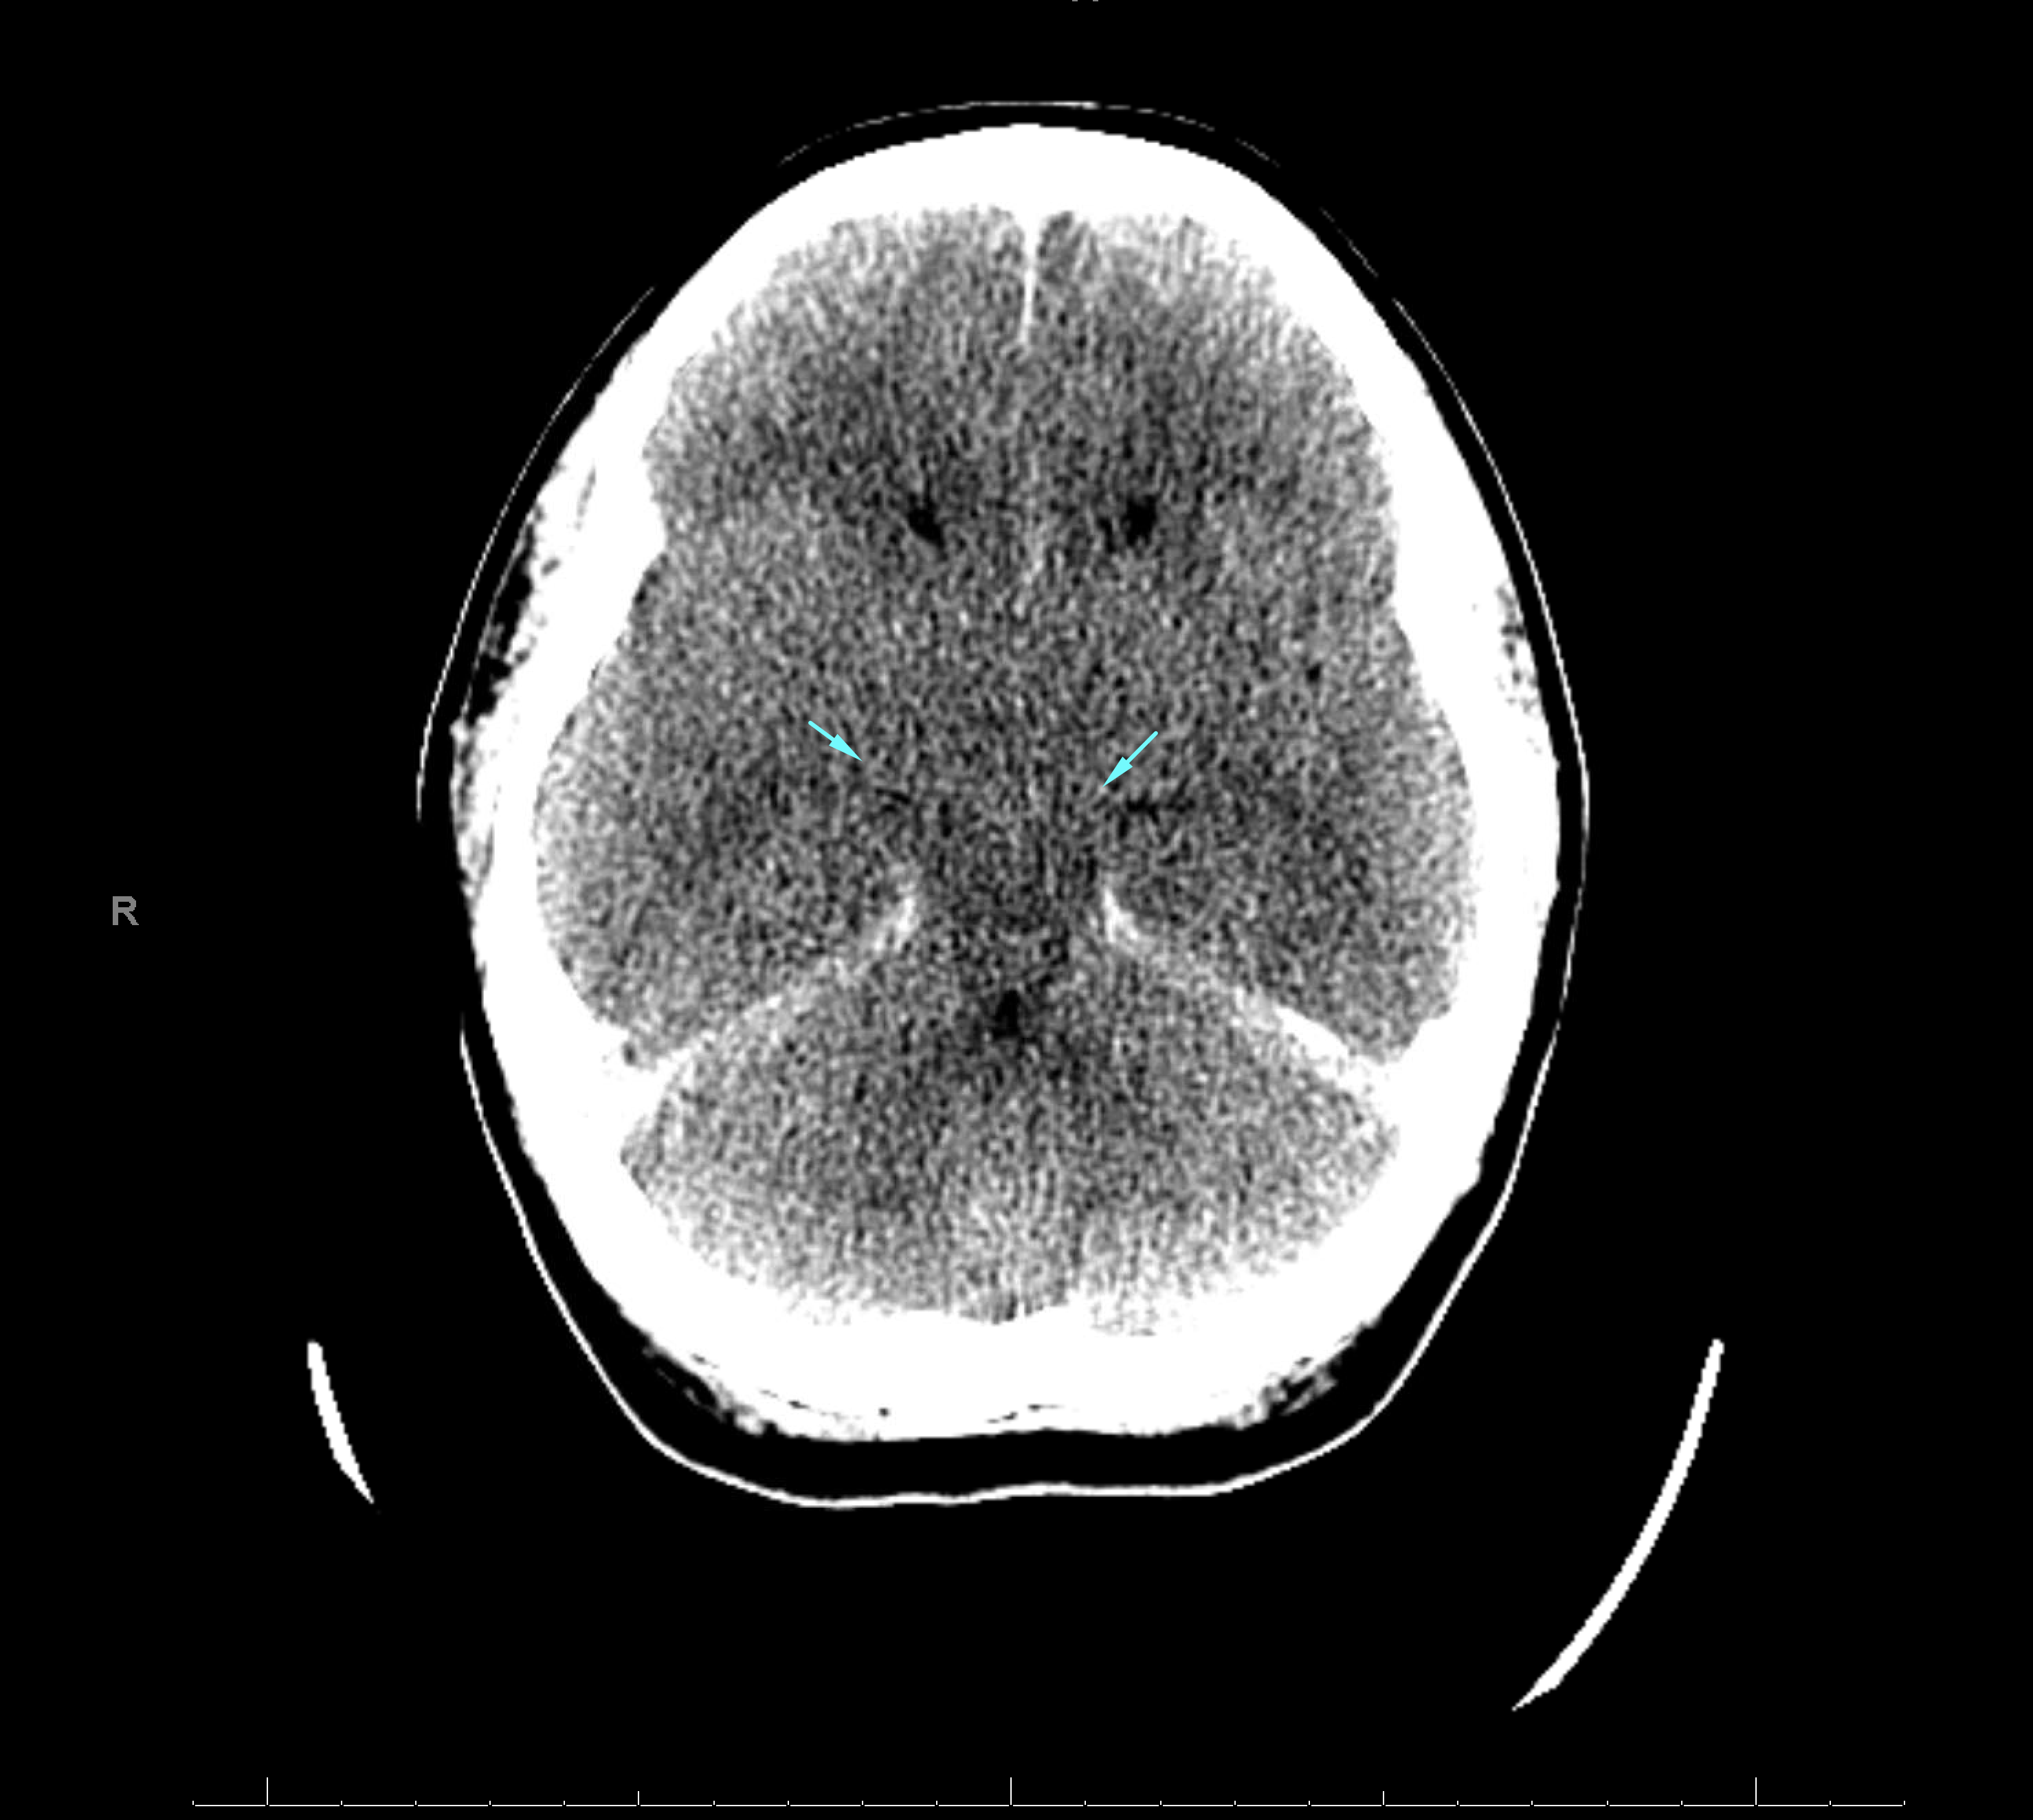

Age: 16

Sex: Female

Indication: Acute respiratory arrest, evaluate for brain death

Radiotracer: Tc99m ECD

Sample ReportNo evidence of intracranial perfusion. While not diagnostic in itself, this finding would support a clinical diagnosis of brain death.